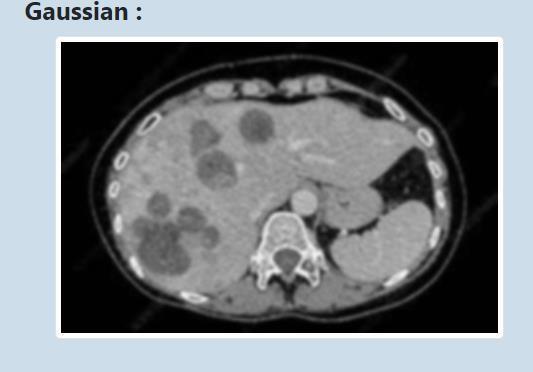

Figure 4 : Applicationofgaussianfilter

Figure 4 shows the filtered image by using gaussian filter. This noise in the image is produced if the image is not captured properly. In the case, CT scan image of patient is nottakenproperlyduetosomemovements,therewill bea noise in the image and a unwanted distortions in the original image which cannot be used for the further processes as it does not produce the properresult.So,itis important to remove the noise if there is a noise else not necessary.Ingaussianfilteragaussiankernelof3x3matrix isconvouledwiththeinputimage.